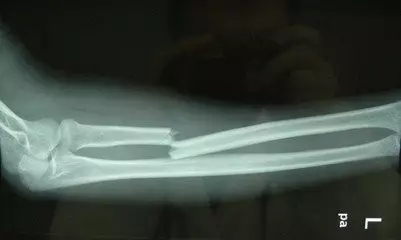

笔者有一远方亲戚,在干活时胫骨被砸,严重骨折。当地乡镇医院医疗水平有限,拒绝收治,便只能去县医院接受了手术治疗,恢复得较理想,但未痊愈。住院一个半月后便回家了,在家中因行走时闪了一下伤处便复发了,伤口处皮肤破损,流出了脓血,疼痛十分严重,不能动弹。由于距离医院较远,便只能派人去请来当地的一个接骨匠(在农村,会有一些人专门跟随有经验的医生学习接骨,这些人成为接骨匠)。这个接骨匠看了之后,也没说什么,简单地处理了一下伤口,用夹板固定了骨折处。然后让伤者家属和他一起回家去配药。